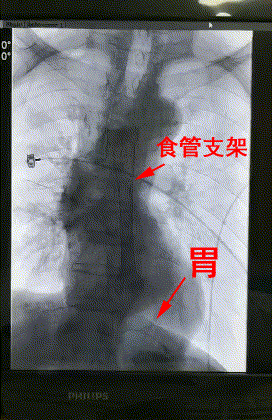

3月28日上午,楊阿姨被送進了介入手術室,李旭丹主任等專家根據術前方案上台施術,先采用飛利浦DSA開展食道造影,明确食道狹窄端及瘘口位置,後經導絲引入食管支架釋放于準确位置。DSA顯示支架成功擴張食管狹窄端并封閉瘘口,順利完成手術。

術後患者無不良反應,生命體征平穩,24小時後能夠進食。楊阿姨及其家屬非常感激。

△術後DSA造影顯示:支架成功擴張食管狹窄端并封閉瘘口。

李旭丹主任介紹,對食道癌晚期出現的食管狹窄或食管氣管瘘等導緻不能進食問題,及時采用DSA下食管支架置入術可有效延長患者生存期和改善生存質量,是一種非常理想的治療方案。